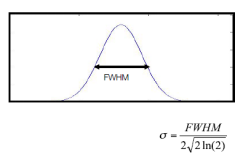

对图像进行空间滤波时,我们经常使用高斯核(Gaussian kernel),该平滑核的尺寸(平滑范围)由半高宽(full width at half maximum, FWHM)决定。如下图 3所示,半高宽是指:分布函数在其峰值一半位置上的峰宽。对于高斯分布而言,其半高宽与标准差存在关系:

图3半高宽

图3半高宽

根据匹配滤波器(matched filter)的设计原则,与信号尺度相匹配的滤波器可以为我们提供最大信噪比,所以如果我们知道激活区的确切尺度,就应该以该尺度进行平滑,这样可以保留信号幅度并降低噪声。但通常平滑核的尺寸是在观察激活区之前就根据先验知识确定的,所以我们不大可能使得该尺寸与激活区尺度完全匹配。另外,我们通常采用同样尺寸的平滑核对整个大脑图像进行平滑,但在不同脑区,激活区的尺度不尽相同。为了避免这样的问题,可以采用自适应平滑(adaptive smoothing)的方法,涉及非平稳空间的Gaussian-Markov随机场,实现空间和时间的平滑。

注:通常来说,平滑核的选取在不同的实验要求下有不同的标准,增加平滑核尺寸可导致检测到更大范围的激活区域,但会减弱对较小激活区域的检测能力,如下图 4所示。一般选取两倍于体素尺寸的平滑核,即若体素大小为3×3×3,一般选取FWHM=6mm。